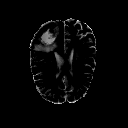

The goal of unsupervised anomaly segmentation (UAS) is to detect the pixel-level anomalies unseen during training. It is a promising field in the medical imaging community, e.g, we can use the model trained with only healthy data to segment the lesions of rare diseases. Existing methods are mainly based on Information Bottleneck, whose underlying principle is modeling the distribution of normal anatomy via learning to compress and recover the healthy data with a low-dimensional manifold, and then detecting lesions as the outlier from this learned distribution. However, this dimensionality reduction inevitably damages the localization information, which is especially essential for pixel-level anomaly detection. In this paper, to alleviate this issue, we introduce the semantic space of healthy anatomy in the process of modeling healthy-data distribution. More precisely, we view the couple of segmentation and synthesis as a special Autoencoder, and propose a novel cycle translation framework with a journey of 'image->semantic->image'. Experimental results on the BraTS and ISLES databases show that the proposed approach achieves significantly superior performance compared to several prior methods and segments the anomalies more accurately.